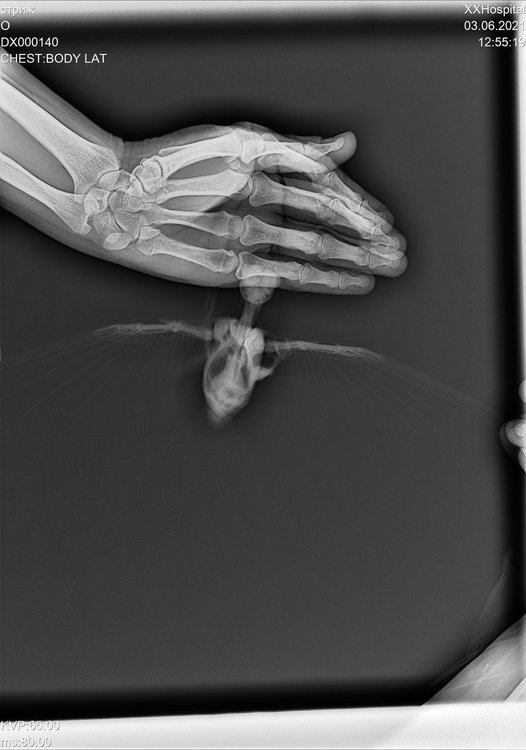

сделали ренген стрижу, только специалистов по птицам в клинике нет.. хотя бы знать нет ли  ничего серьезного.. ехать в москву нет возможности.

DX000140_4.jpg

@валена простите, не видела раньше вашу тему. Что-то с оповещениями не то. К сожалению, по данному рентгену можно очень мало чего сказать. Он совершенно бездарен.

Разве что если переделать? Стрижа для снимка кладут на спинку и полностью  раскрывают его крылышки. Нужен только 1 снимок.